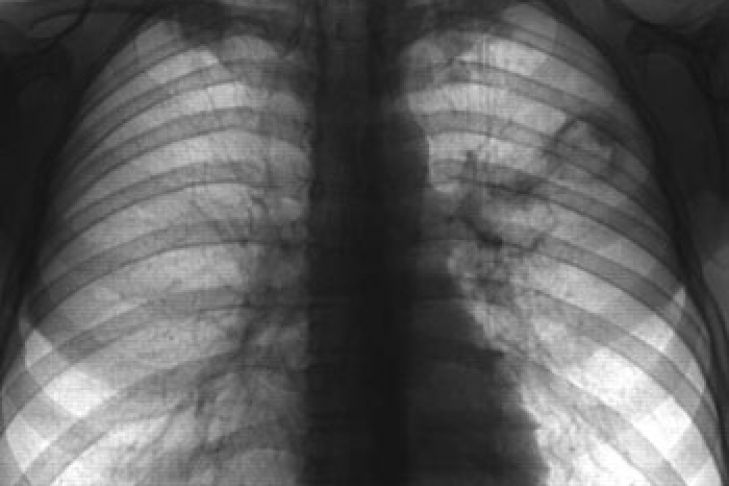

Судебно-медицинская экспертиза установила, что мужчина, тело которого было найдено возле Майдана Независимости в Киеве, скончался от туберкулеза легких. Об этом сообщили в пресс-службе киевской милиции.

«Закончилась судмедэкспертиза. По заключению медиков, это был туберкулез легких, который вызвал внутреннее кровотечение», - рассказали в пресс-службе ведомства.

Вместе с тем, в пресс-службе прокуратуры Киева уточнили, что предварительная причина смерти – туберкулез легких открытой формы.